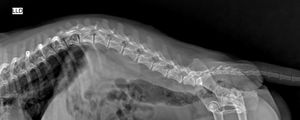

O Thor, da raça lhasa apso, tem 6 aninhos, é muito alegre e brincalhão, e mesmo com todas as restrições que colocamos, infelizmente a coluninha dele não tolerou esse estilo de vida agitado, há 1 semana ele amanheceu com dor e mancando, achamos que fosse mais uma de suas crises que com medicação e repouso ficaria tudo bem, só que quase 2 dias depois, ele perdeu os movimentos dos membros traseiro (plegia), levamos ao vet o que evidenciou uma provável hérnia comprimindo a medula espinal, com isso ele precisa realizar alguns exames para confirmação e o quadro é possivelmente reversível apenas com cirurgia, que o quanto antes for realizada, melhor será seu prognóstico.

E devido ao alto custo, infelizmente no momento não temos condições de arcar com todo o processo cirúrgico que é a ÚNICA forma de tratamento para o caso dele, e não queria ter que discutir eutanásia, mas não desistirei até ter feito tudo ao alcance. Hoje ele se encontra utilizando fraldas, e muito debilitado.

Realizaremos a cirurgia, e após, as sessões de fisioterapia para recuperação dos movimentos das pernas traseiras.